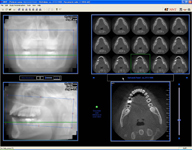

NewTom Giano

Jedná se o nejnovějším přístroj ze skupiny dentálních hybridních CBCT (3D) + 2D (pan i ceph) systémů. Opět umožňuje na základě jediného snímkování vytvořit všechny typy RTG zobrazení, které jsou pro lékaře potřebné. Používaná technologii tzv. „kuželového paprsku“ a speciální senzory pro minimální zátěž při snímkování pacienta.

Vyšetření pomocí tohoto přístroje (nebo

3D DVT - NewTom) a získaná data používáme

pro každou implantaci, dále ve stomatochirurgii (zlomeniny čelistí, zuby moudrosti, cysty, onemocnění čelistního kloubu), ortodoncii (retinované zuby, nadpočetné zuby), parodontologii atd.